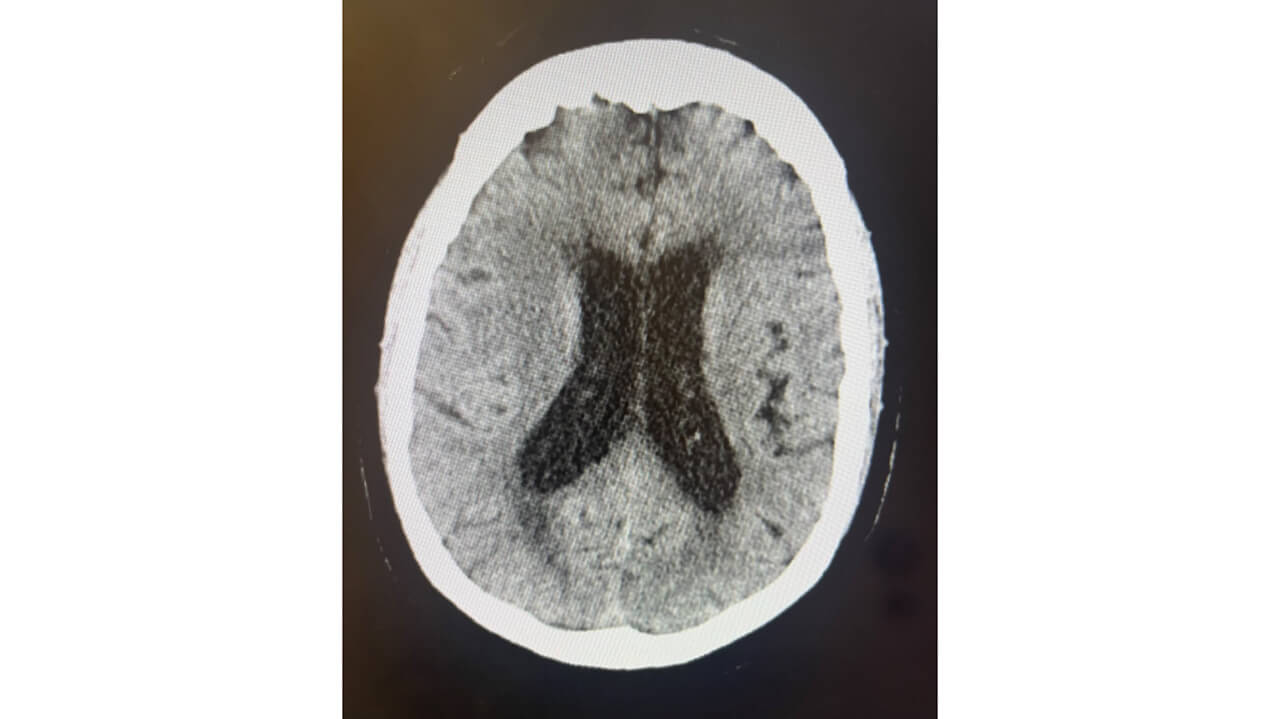

CT head w/o contrast 10/13 11am

• Recurrent soft tissue tumor in the suprasellar cistern measuring 4.0 x 4.5 cm​

• Exerting mass effect on the third ventricle with borderline increased ventricular volume ​

CT head w/o contrast 10/13 10pm

• Findings are concerning for obstructive hydrocephalus

CT head w/o contrast 10/17​

• Sellar / suprasellar lesion has decreased in size now measuring approximately 3.6 x 3.1 cm​

• Repeat head CT w/o contrast demonstrated decreased size of the ventricular system​

• Sella and suprasellar lesion now measuring 3.6 x 3.1 cm in size​